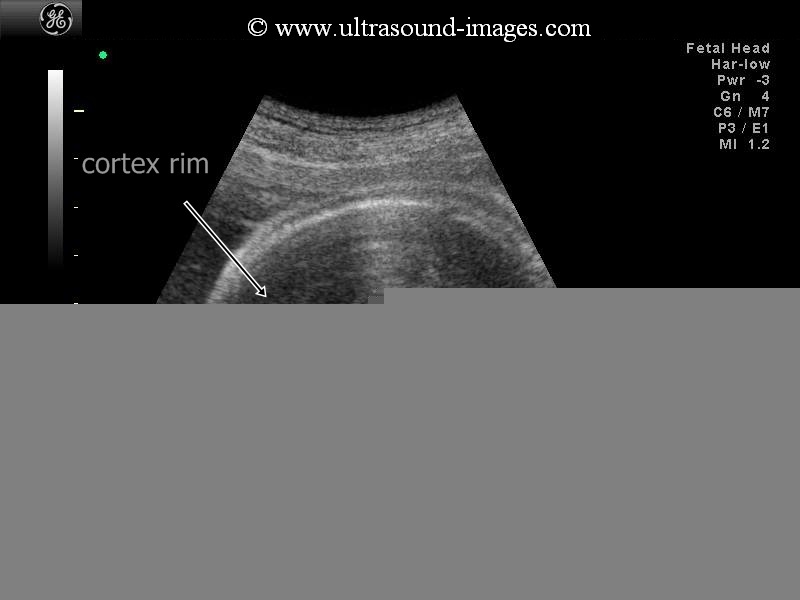

3-D alobar holoprosencephaly

This second trimester fetus shows all the features of alobar holoprosencephaly. The 3-D ultrasound images of the fetal face show absence of the nose or arhinia. In addition, there is a rudimentary single eye seen lower down in the midline. This is known as cyclopia and the fetus is said to be a cyclops. In addition, the 2-D ultrasound image of the fetal brain shows a single common ventricle or what is known as a mono-ventricle running from one side to the other with absence of midline structures such as the falx cerebri. Besides, both the thalami appear to be fused forming a single structure. Also, surrounding the mono ventricle is a rim of cerebral cortical tissue. All these ultrasound features are suggestive of a severe case of holoprosencephaly also known as alobar holoprosencephaly. The above ultrasound images of alobar holoprosencephaly are courtesy of Dr. Rami Barakat, MD.